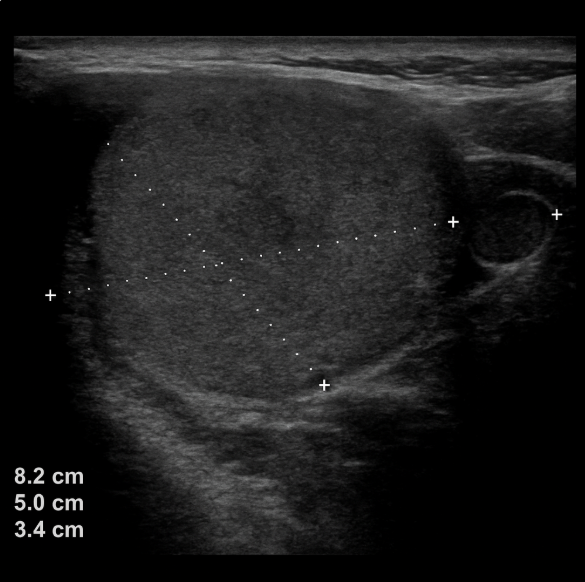

Neck ultrasound: Thyroid gland: not visible, right thyroid bed with fibro-fatty changes. A mass measuring 8.2 x 50 x 3.4 cm is observed in the left thyroid bed. Submaxillary and parotid glands: no evidence of lesions in cervical lymph nodes; some ovoid nodular images are identified, with a short axis less than 10 mm, hypoechoic and thin cortex, retaining their hilum with an echogenic center (Figure 5).

Neck ultrasound. Right thyroid bed with fibro-fatty changes.